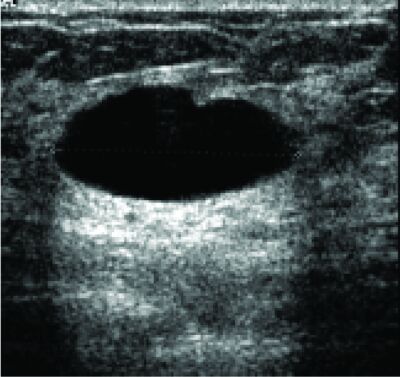

Echografie

Echografie is van groot belang bij palpabele afwijkingen, 15, 17 maar niet geschikt als er geen gelokaliseerde afwijking aanwezig is: een echogram is een doorsnede. Echografie is geschikt om onderscheid te maken tussen een cyste (figuur 4) en een solide tumor. Blijkt het om een solide tumor te gaan, dan zal een röntgenoloog in de regel kunnen onderscheiden tussen een benigne (meestal fibroadenoom) en een maligne tumor met een zeer hoge sensitiviteit (93%) en specificiteit (95%). 19[E] Het enige probleem vormt het enkele medullaire of ductale carcinoom dat op een fibroadenoom lijkt. De negatief voorspellende waarde (99%) van echografie bij palpabele afwijkingen is zeer hoog.